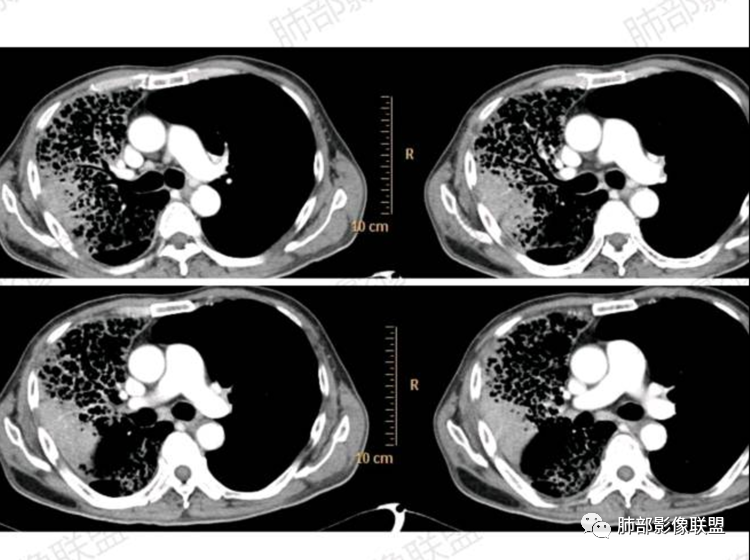

CT:右肺弥漫实变影及磨玻璃影,内见小网格影及蜂窝影,病灶由胸膜下向外进展,明显均匀强化。

实变区在胸膜下,部分边缘膨隆,凸向胸壁

似有栽赃嫌疑

支气管在近端堵塞,或狭窄

实变近端

边缘膨隆+收缩

2.影像显示右肺较广泛蜂窝样阴影,上肺及下肺为主,未见液平及重力分布趋势。其中上叶后段及下叶后基底段近胸膜下可见实性密度区,实性密度区强化明显,周边特征掩盖不清。

5.纵隔轻度右移,提示右肺体积整体轻度减小。

6.纵隔未见增大淋巴结。右肺门掩盖。